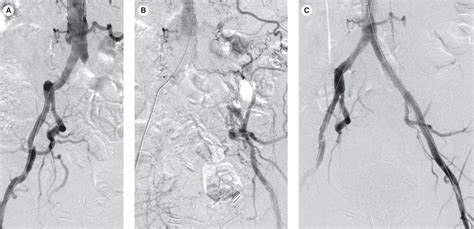

Catheter Angiography Invasive gold standard Used primarily during intervention to visualize flow while treating the blockage.

• Endovascular Therapy: This includes balloon angioplasty and stenting. It is minimally invasive, typically involving a small puncture in the groin to access the vessel, and allows for a quicker recovery time.